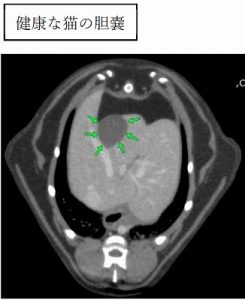

棉花糖ちゃんの胆嚢は壁が腫れているため白く目立っており、さらに胆嚢から肝臓へ続く管がすべて拡張して蛇行しています。

健康な猫ちゃんの膵臓ははっきりとして白い実質なのに比べ、棉花糖ちゃんでは膵臓のまわりにモヤモヤとした「毛羽立ち」のようなものが見えます。これは膵臓に激しい炎症や壊死が起こった場合に認められます。